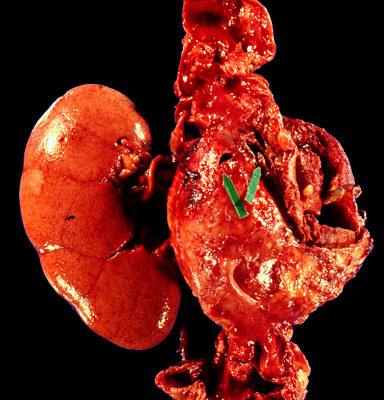

Ruptured aneurysm of the abdominal aorta

The arrows point to the sites of rupture of this large perirenal

aneurysm

.